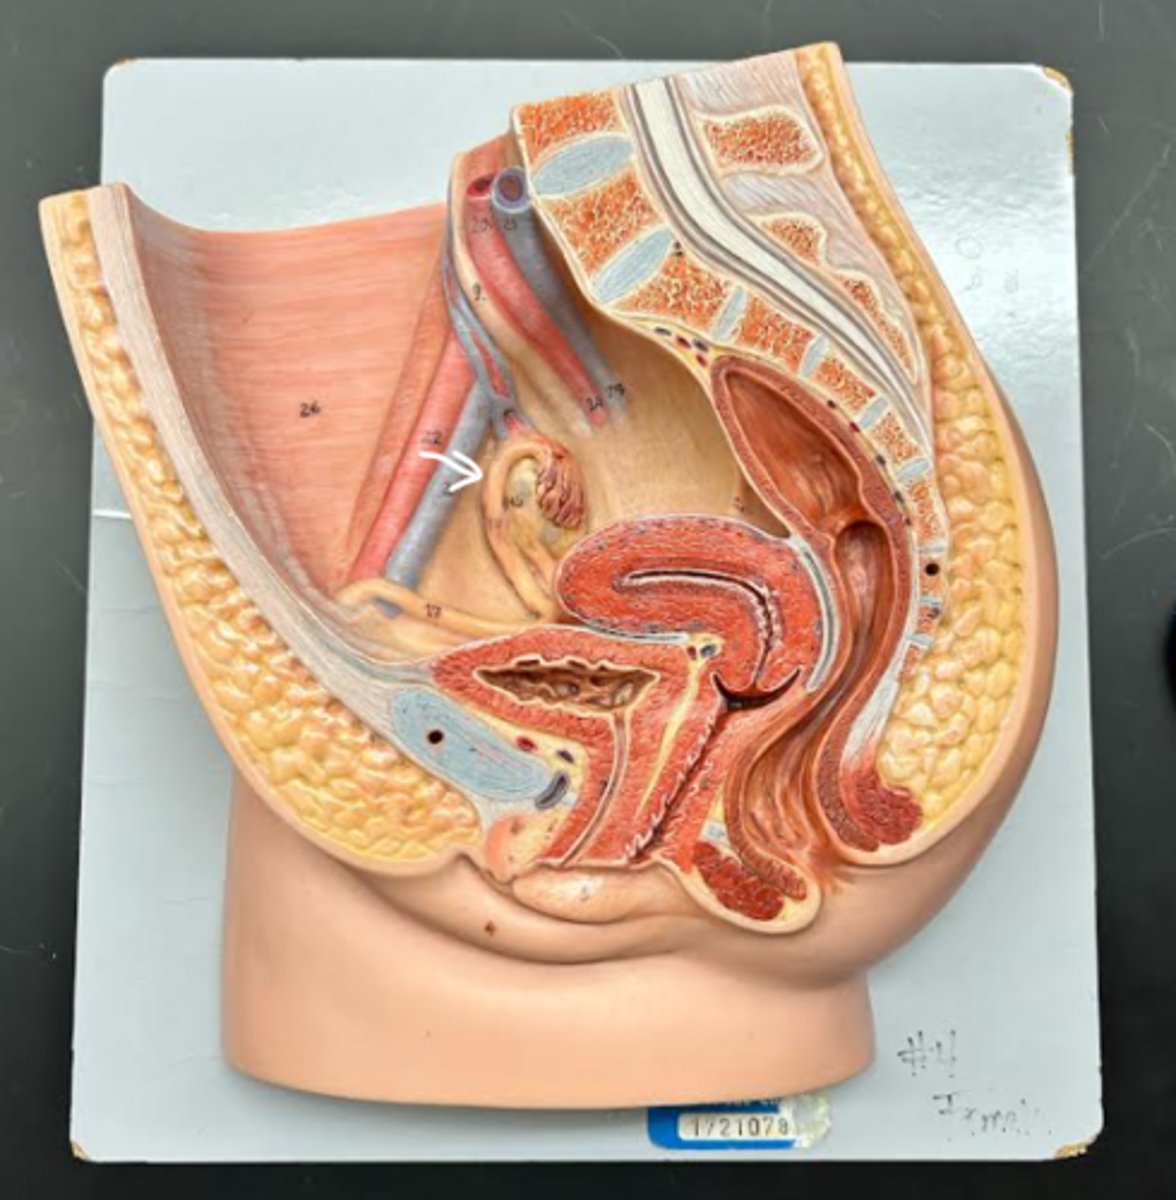

Vagina

Vaginal orifice

Hymen

Vaginal fornix

Ovary

Fallopian tube

Fimbriae

Infundibulum

Ampulla

Isthmus

Uterus

Fundus

Body of uterus

Cervix

Internal os

Cervical canal

External os

External urethral orifice